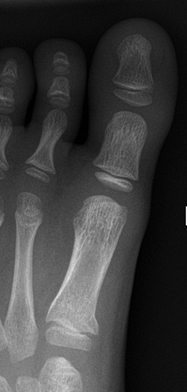

Avulsion fracture of base of fifth metatarsal

Avulsion fracture at base of fifth metatarsal

• Follow up Orthopaedic Fracture clinic 7- 10 days.

• If 4th and 5th inter-metatarsal joint involved (Jones Fracture), not suitable for CAM Boot.